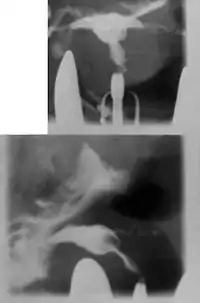

Hysterosalpingography of a T-shaped uterus. | |

Women are often diagnosed with this condition after several failed pregnancies, proceeded by exploratory diagnostic procedures, such as magnetic resonance, sonography, and particularly hysterosalpingography.[6][7][8] In such studies, a widening of the interstitial and isthmus of uterine tube is observed, as well as constrictions or narrowing of the uterus as a whole, especially the lower and lateral portions, hence the "t" denomination. The uterus might be simultaneously reduced in volume, and other abnormalities might be concomitantly present.[9]